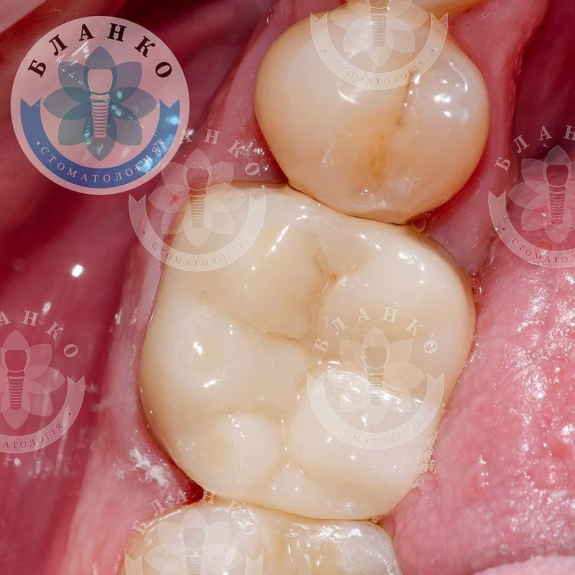

— сняты оттиски и изготовлена высокопрочная, гипоаллергенная и высокоэстетичная коронка из диоксида циркония.

✳️Итого, мы наблюдаем интересную ситуацию.

На примере этого клинического случая мы отчетливо видим, что экономить на своём здоровье нежелательно, потому что зуб — не туфель, в урну не выбросишь.